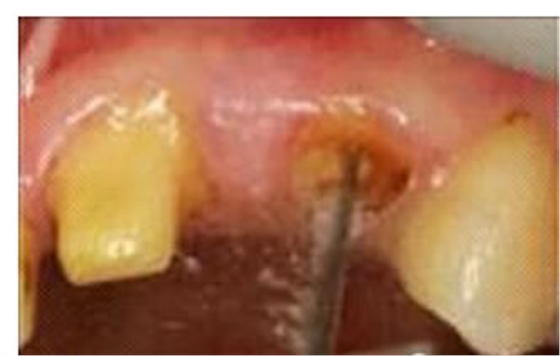

圖3:根管內(nèi)殘留物

圖4:超聲去除根管殘留物。

根管壁殘留物的存在直接影響著纖維樁的粘接和固位,是纖維樁脫落的主要原因之一。由于圓形的根管鉆和根管形態(tài)不完全一致,終鉆預(yù)備完成后大多情況下樁道側(cè)壁會(huì)有不同程度的牙膠和封閉劑等殘留物附著(圖 3)。因此,建議X線檢查根管預(yù)備情況,選用超聲潔牙機(jī)更換較細(xì)工作尖進(jìn)入根管,徹底去除樁道根管壁上附著的殘留物(圖4)。使用根管銼去除殘留物時(shí),很難清除干凈;禁止使用牙膠溶劑如丁克除、氯仿等有機(jī)溶劑去除殘留物,以免破壞根尖區(qū)牙膠的封閉,或有機(jī)溶劑粘附于根管壁形成蠟?zāi)ざ绊懻辰印?/p>